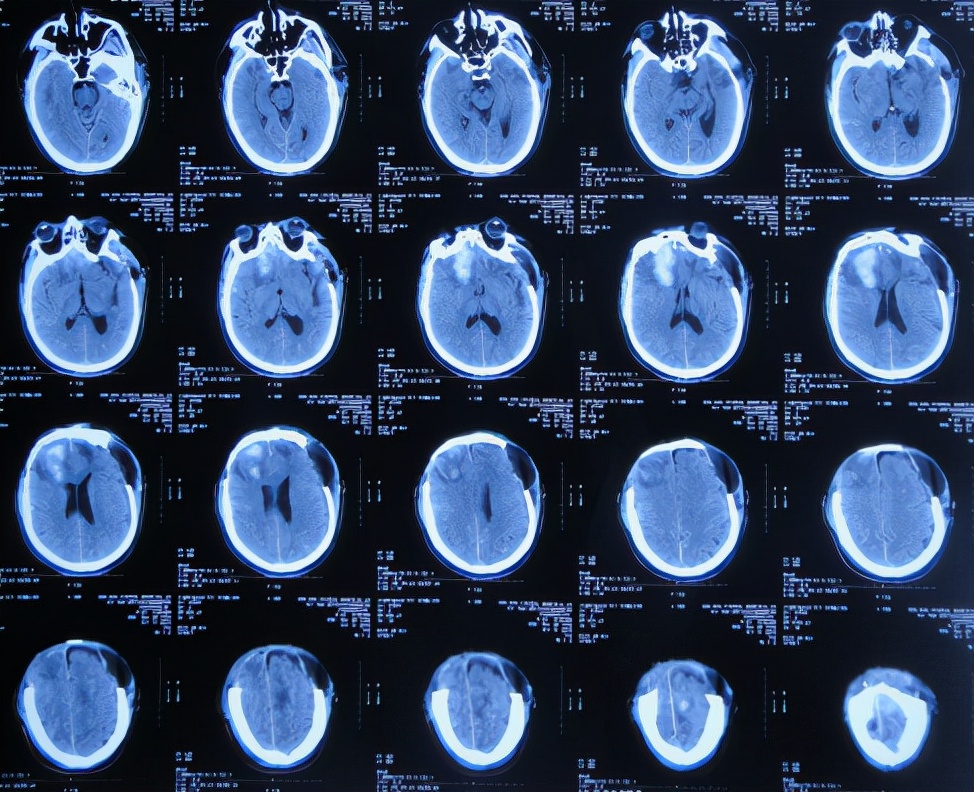

继续治疗1周时间内,曾3次复查头颅CT( 图-5、图-6、图-7 )均示脑膨出逐渐加重的趋势,仍有积血;期间给予腰大池引流。

图-5: 2019年10月26日头颅CT

图-6: 2019年10月29日头颅CT

图-7: 2019年10月31日头颅CT

开颅术后14天即2019年11月3日,虽仍有些积血,但脑膨出有好转( 图-8 ),意识也变清。

图-8: 2019年11月3日头颅CT

开颅术后18天即2019年11月7日,脑膨出进一步好转( 图-9 )。

图-9: 2019年11月7日头颅CT

开颅术后26天即2019年11月15日,查头颅CT示积血基本消失,脑膨出变正常( 图-10 )。

图-10: 2019年11月15日头颅CT

开颅术后30天即2019年11月19日,出现走路不稳,查颈椎核磁( 图-11 )后认为无明显异常。

图-11: 2019年11月19日腰椎核磁

开颅术后33天即2019年11月21日,查头颅CT( 图-12 )后认为无明显异常随后出院。

图-12: 2019年11月21日头颅CT

但第1家医院出院后13天即2019年12月4日,出现尿*禁失**,到当地的邯郸市临漳县某医院查头颅CT( 图-13 )后,转给给予开颅手术的医院医生,医生认为与出院时无明显变化,但之后的6天时间内出现走路不稳,大小便*禁失**加重的症状。

图-13: 2019年12月4日头颅CT

为求进一步有效治疗,于第1家医院出院后19天即2019年12月10日,住入第2家的北京某解放军的三甲医院,入院次日查头颅CT( 图-14 )后认为是脑积水。

图-14: 2019年12月11日头颅CT

入院3天即2019年12月13日,同时进行了颅骨修补术+脑室腹腔分流术。术后3天即2019年12月16日,在搀扶下可以下床走路活动,查头颅CT示颅骨修补术后+脑室引流术后状态( 图-15 )。

图-15: 2019年12月16日头颅CT